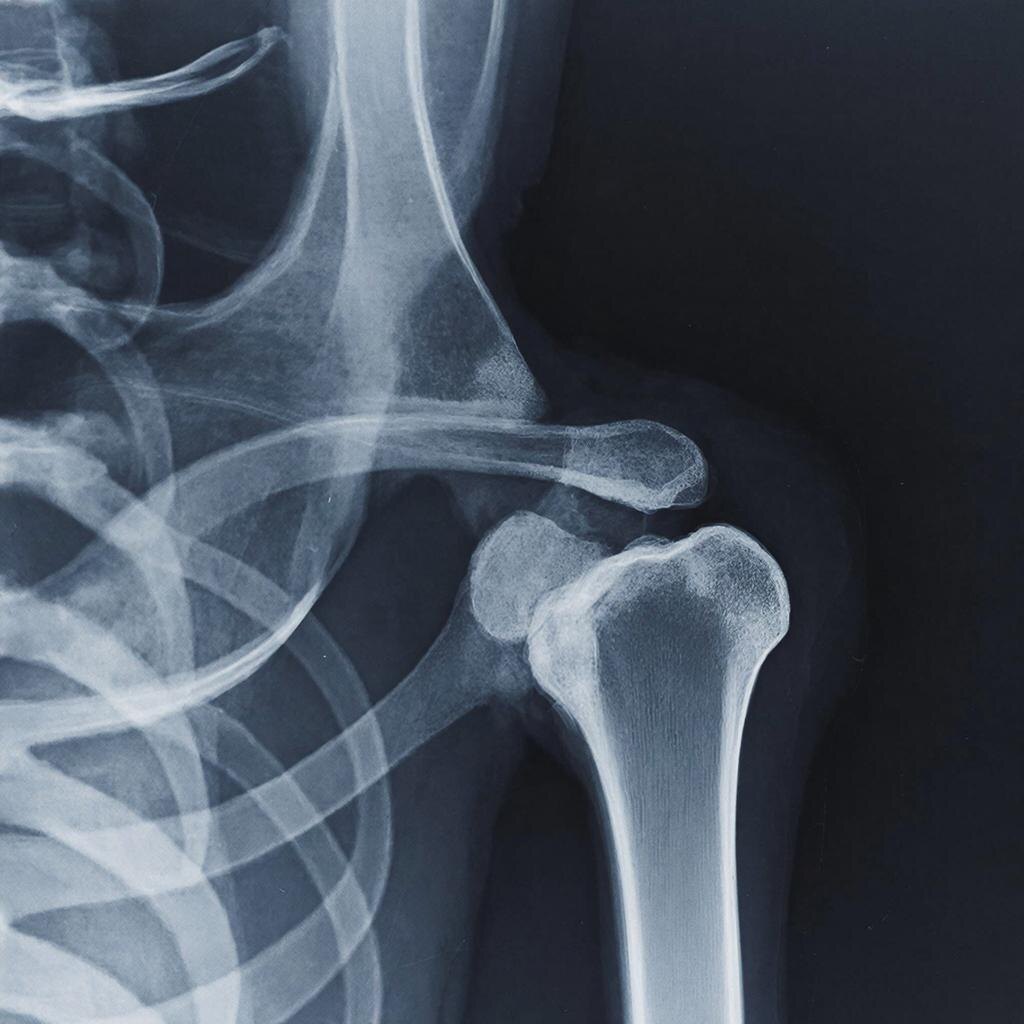

Новое исследование, проведённое специалистами из Университета Осаки (OMU), показало, что восстанавливать кости можно и при помощи жировой ткани. Это позволит изменить подход к лечению переломов и повысить прочность костей при остеопорозе.

В рамках нового исследования учёные использовали стволовые клетки, полученные из жировой ткани, развив их частично до костной ткани. Далее эти клетки собрали в сферические кластеры, которые и способствовали регенерации тканей.

У группы крыс, которую лечили остеогенными сфероидами, значительно увеличилась костная масса, улучшились показатели сращения и механическая прочность. Согласно гистологическому анализу, происходило усиленное образование новой костной ткани, интеграция β-трикальцийфосфата.

Также специалисты подтвердили, что стволовые клетки жировой ткани в точке восстановления выживали.